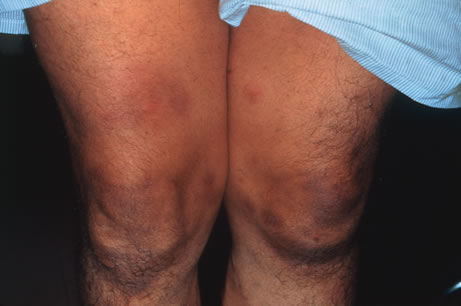

Kaposi's sarcoma is much more frequent in male homosexuals and bisexuals than in other patients with AIDS. Cutaneous lesions are usually red or violaceous, palpable, and nonblanching papules, nodules, or plaques, often appearing on the hard palate, nose, eyelid, and conjunctiva (Fig. 11). Visceral and lymph node involvement is common and often clinically silent. Biopsy specimens show proliferation of small, incompletely formed blood vessels lined by unusually large endothelial type cells, with extravasated red blood cells and infiltrates of spindle-shaped cells. Chemotherapy with etoposide, Vinca alkaloids, or interferon-α may be indicated in advanced cases.28